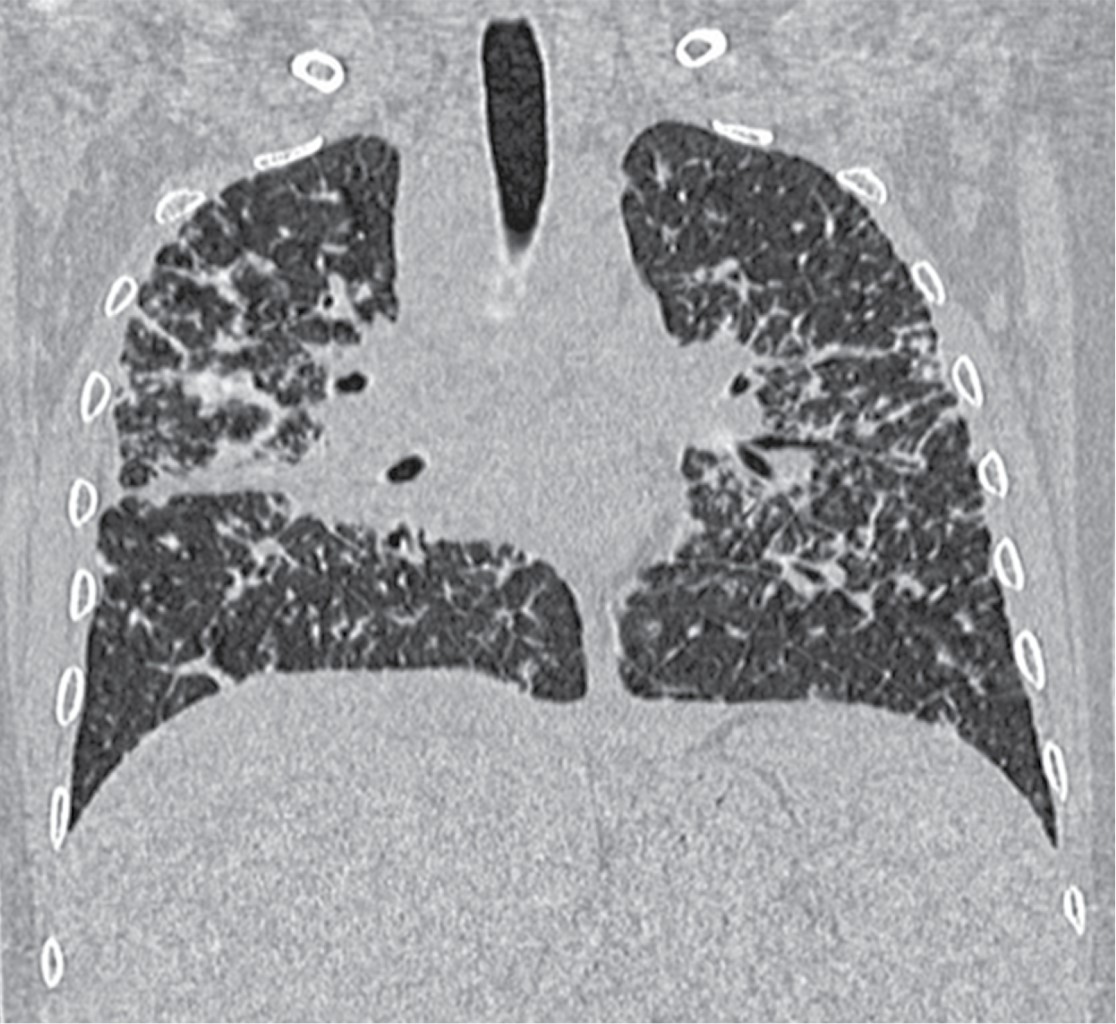

La tomografía axial computarizada de alta resolución (TACAR) pulmonar inicial mostró un patrón retículo nodular fino difuso con engrosamiento bronquial discreto y crecimientos nodulares parahiliares bilaterales (Figura 2). La espirometría mostró un patrón restrictivo sin respuesta significativa al uso del broncodilatador.

La radiografía de tórax mostró ensanchamiento mediastinal y un patrón intersticial grueso a expensas de intersticio perilobulillar bilateral y difuso, casi simétrico con algunas imágenes nodulares también difusas (Figura 9). En la TACAR contrastada se corrobora el patrón intersticial perilobulillar con nódulos difusos con discreto predominio subpleural así como zonas de atelectasia bilateral subpleurales y en lóbulo medio (Figura 10). En la ventana mediastinal se demuestran crecimientos ganglionares paratraqueales de predominio derecho, en ventana aortopulmonar y axilar bilateral. A nivel abdominal lesiones nodulares hipodensas múltiples hepatoesplénicas sugestivas de granulomas (Figura 11). Se realizó biopsia de piel en cara, la cual mostró dermatitis granulomatosa epitelioide no caseificante, compatible con sarcoidosis (Figura 12).

La radiografía de tórax es anormal en 90% de los casos. Los dos hallazgos más característicos son la linfadenopatía mediastinal bilateral acompañada de enfermedad intersticial nodular del pulmón, éstos sirven para la estadificación de la enfermedad,5,8 siendo la TACAR la herramienta más valiosa para el diagnóstico (Tabla 1).

Nuestros casos se clasifican en el estadio II, ya que en la TACAR se detectó adenopatía hiliar bilateral con infiltrados pulmonares (Tabla 1).

Figura 2

Figura 10